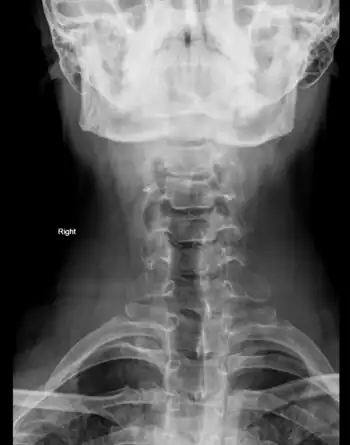

Clay-shoveler fracture

| C7 spinous process. | |

Clay-shoveler's fracture is a stable fracture through the spinous process of a vertebra occurring at any of the lower cervical or upper thoracic vertebrae, classically at C6 or C7.[1] In Australia in the 1930s, men digging deep ditches tossed clay 10 to 15 feet above their heads using long handled shovels.[2] Instead of separating, the sticky clay would sometimes stick to the shovel. At the top of the arc of motion, with the arms extended, the worker may hear a pop and feel a sudden pain between the shoulder blades, unable to continue working.[3][4] The mechanism of injury is believed to be secondary to muscle pull and reflex with force transmission through the supraspinous ligaments. The tremendous force pulls on the spinous process producing an avulsion fracture. The fracture is diagnosed by plain film examination.